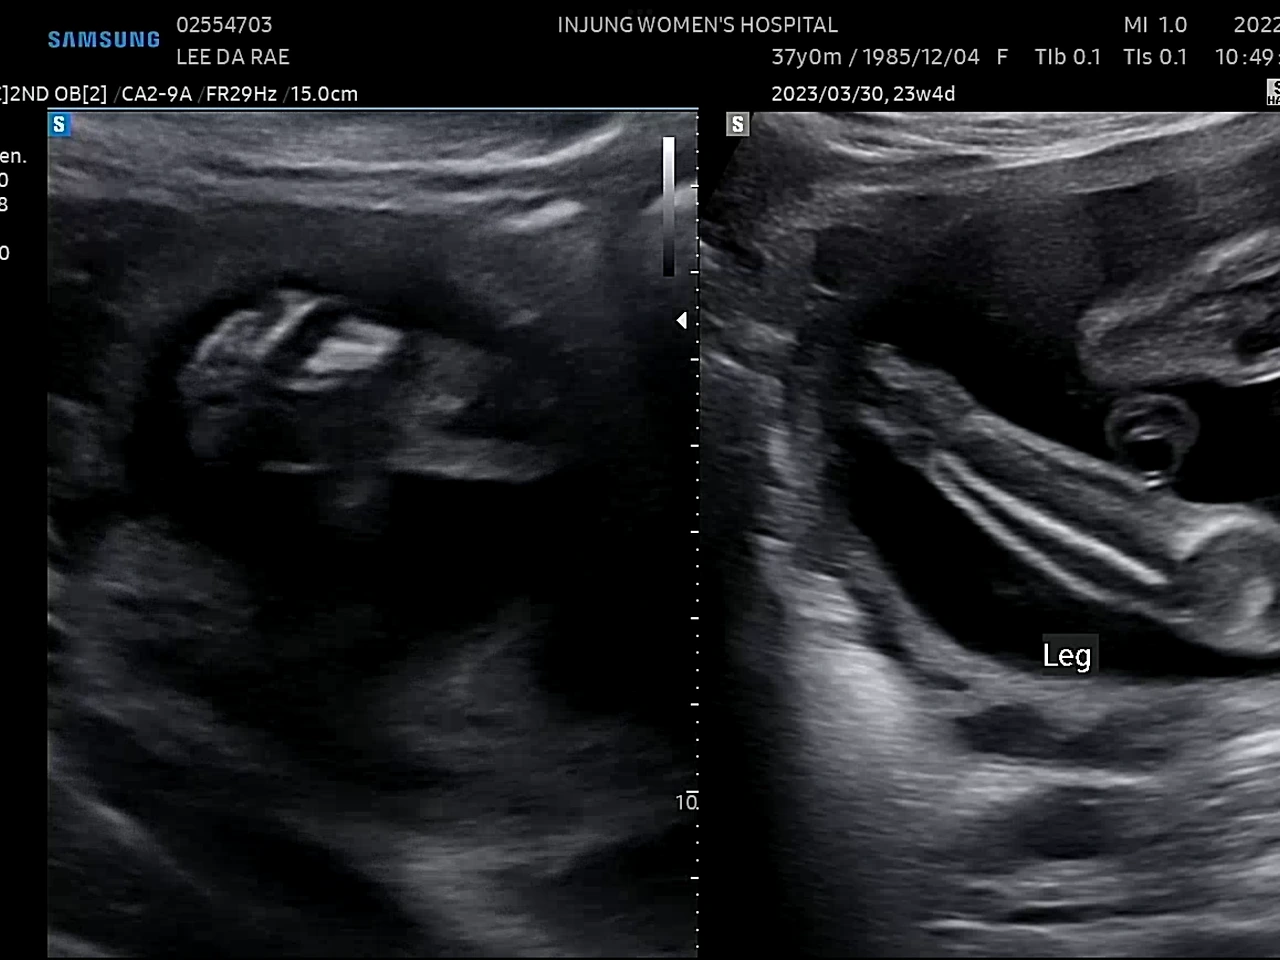

귀여운 손발

23주에 정밀초음파 검사를 받았다. 1차 기형아 검사에서 고위험군으로 나온 후로 모든 검사가 겁이 난다.(니프티검사에서 정상판정) 초음파 선생님(?)이 포도의 심장을 천천히 보시는데 한동안 아무 말씀도 없으시길래 너무 긴장이 됐다. 다행히 포도는 건강했다. 선생님이 아이가 쉬지 않고 움직인다고 하셨다. 아인이 때도 아이가 활발하다는 얘길 들었는데ㅋㅋ 남매라 그런가 비슷하네. 얼른 만나고 싶다 포도야!